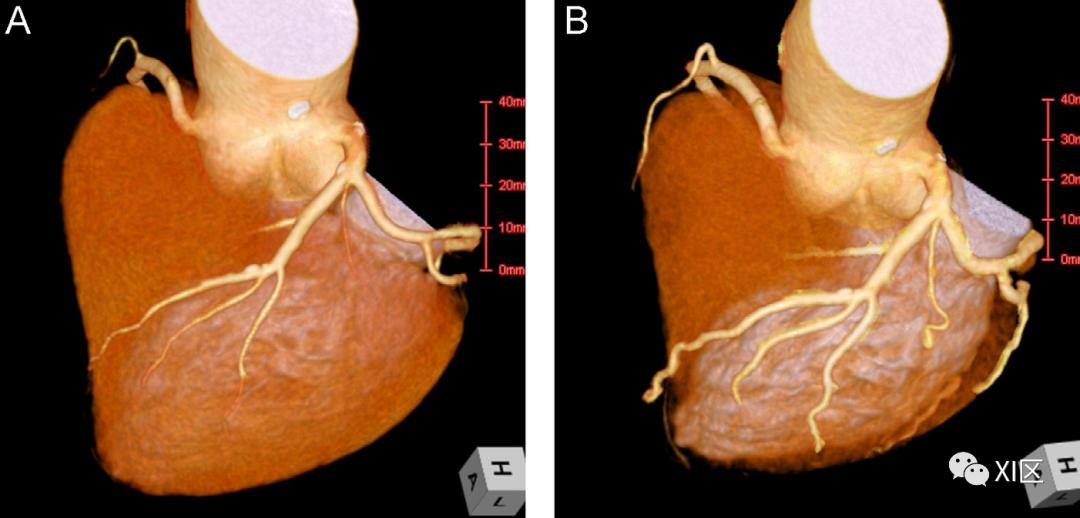

作者回顾性分析了两个历史组(第1组,在CCTA前2分钟单剂量硝酸甘油,第2组,在CCTA前10分钟单次给药)和当前方案组(第3组,在CCTA前2分钟和10分钟单次给药)。每组评估30名患者。两名盲法阅片医生通过直径测量的比较测量冠状动脉腔直径。第三位盲法阅片医生评估冠状动脉节段的图像质量。

研究发现,在中位管腔直径的组水平上存在显著差异。第2组比第1组直径增加0.40 mm(0.20,0.60)和第3组比第1组直径增加0.50 mm(0.30,0.70),第二组和第三组所有节段的中位直径(95%CI)较更高(均P<0.001)。第2组和第3组的管腔直径无明显差异。除第2组和第3组的远端LAD图像质量高于第1组外,各组间图像质量无显著差异。

结果表明,舌下硝酸甘油喷雾剂在10分钟内单次给药,比仅在CCTA前2分钟给药时扩张冠状动脉更大。在两次冠状动脉扩张前10分钟不需要再给药。